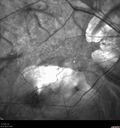

76 year old female with gradually declining vision: VA 20/32 OD; 20/40 OS

Myopic Degeneration - Inferior staphyloma with severe atrophy426 views76 year old with gradual vision loss. 20/32 OD; 20/40 OS00000